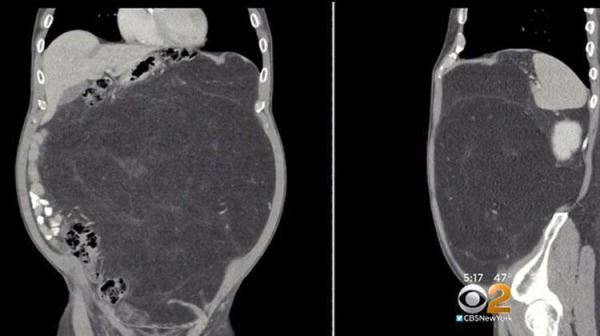

Кевин напугался, что с ним что-то не то и в декабре 2017 года убедил своего лечащего врача отправить его на томографию. Томография показала наличие в животе Кевина крупной опухоли, размером больше футбольного мяча. Кевину был поставлен диагноз липосаркомы. Это раковая опухоль, которая развивается и растет в жировых клетках мягких тканей.

Томография показала, что опасения Кевина насчет инструментов были напрасными, однако там обнаружили куда более страшную вещь — огромная опухоль росла вокруг одной из его почек. Она была самой крупной из всех, что видели врачи этой больницы.

"Одно дело видеть это на снимке, но уже совсем другое держать ее в своих руках", — прокомментировал итоги операции хирург Хулио Тейшейра.

По словам врачей чтобы вырасти такой большой (опухоль весила свыше 12 кг), опухоли надо было расти не менее 10-15 лет. Но теперь у Кевина все позади. Он пошел на поправку и его живот теперь в нормальной форме, а все смещенные опухолью внутренности вернулись на свои места.